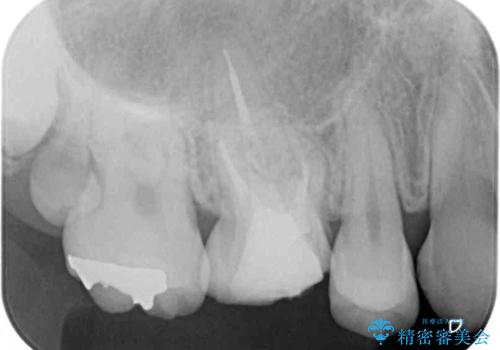

- 虫歯により神経を取り除いた前歯の変色が気になるとのことで来院された患者様です。

レントゲン写真より、歯根の炎症が認められなかったため、ファイバーコアによる土台築製後、オーダーメイドタイプのオールセラミッククラウンにて補綴することとしました。